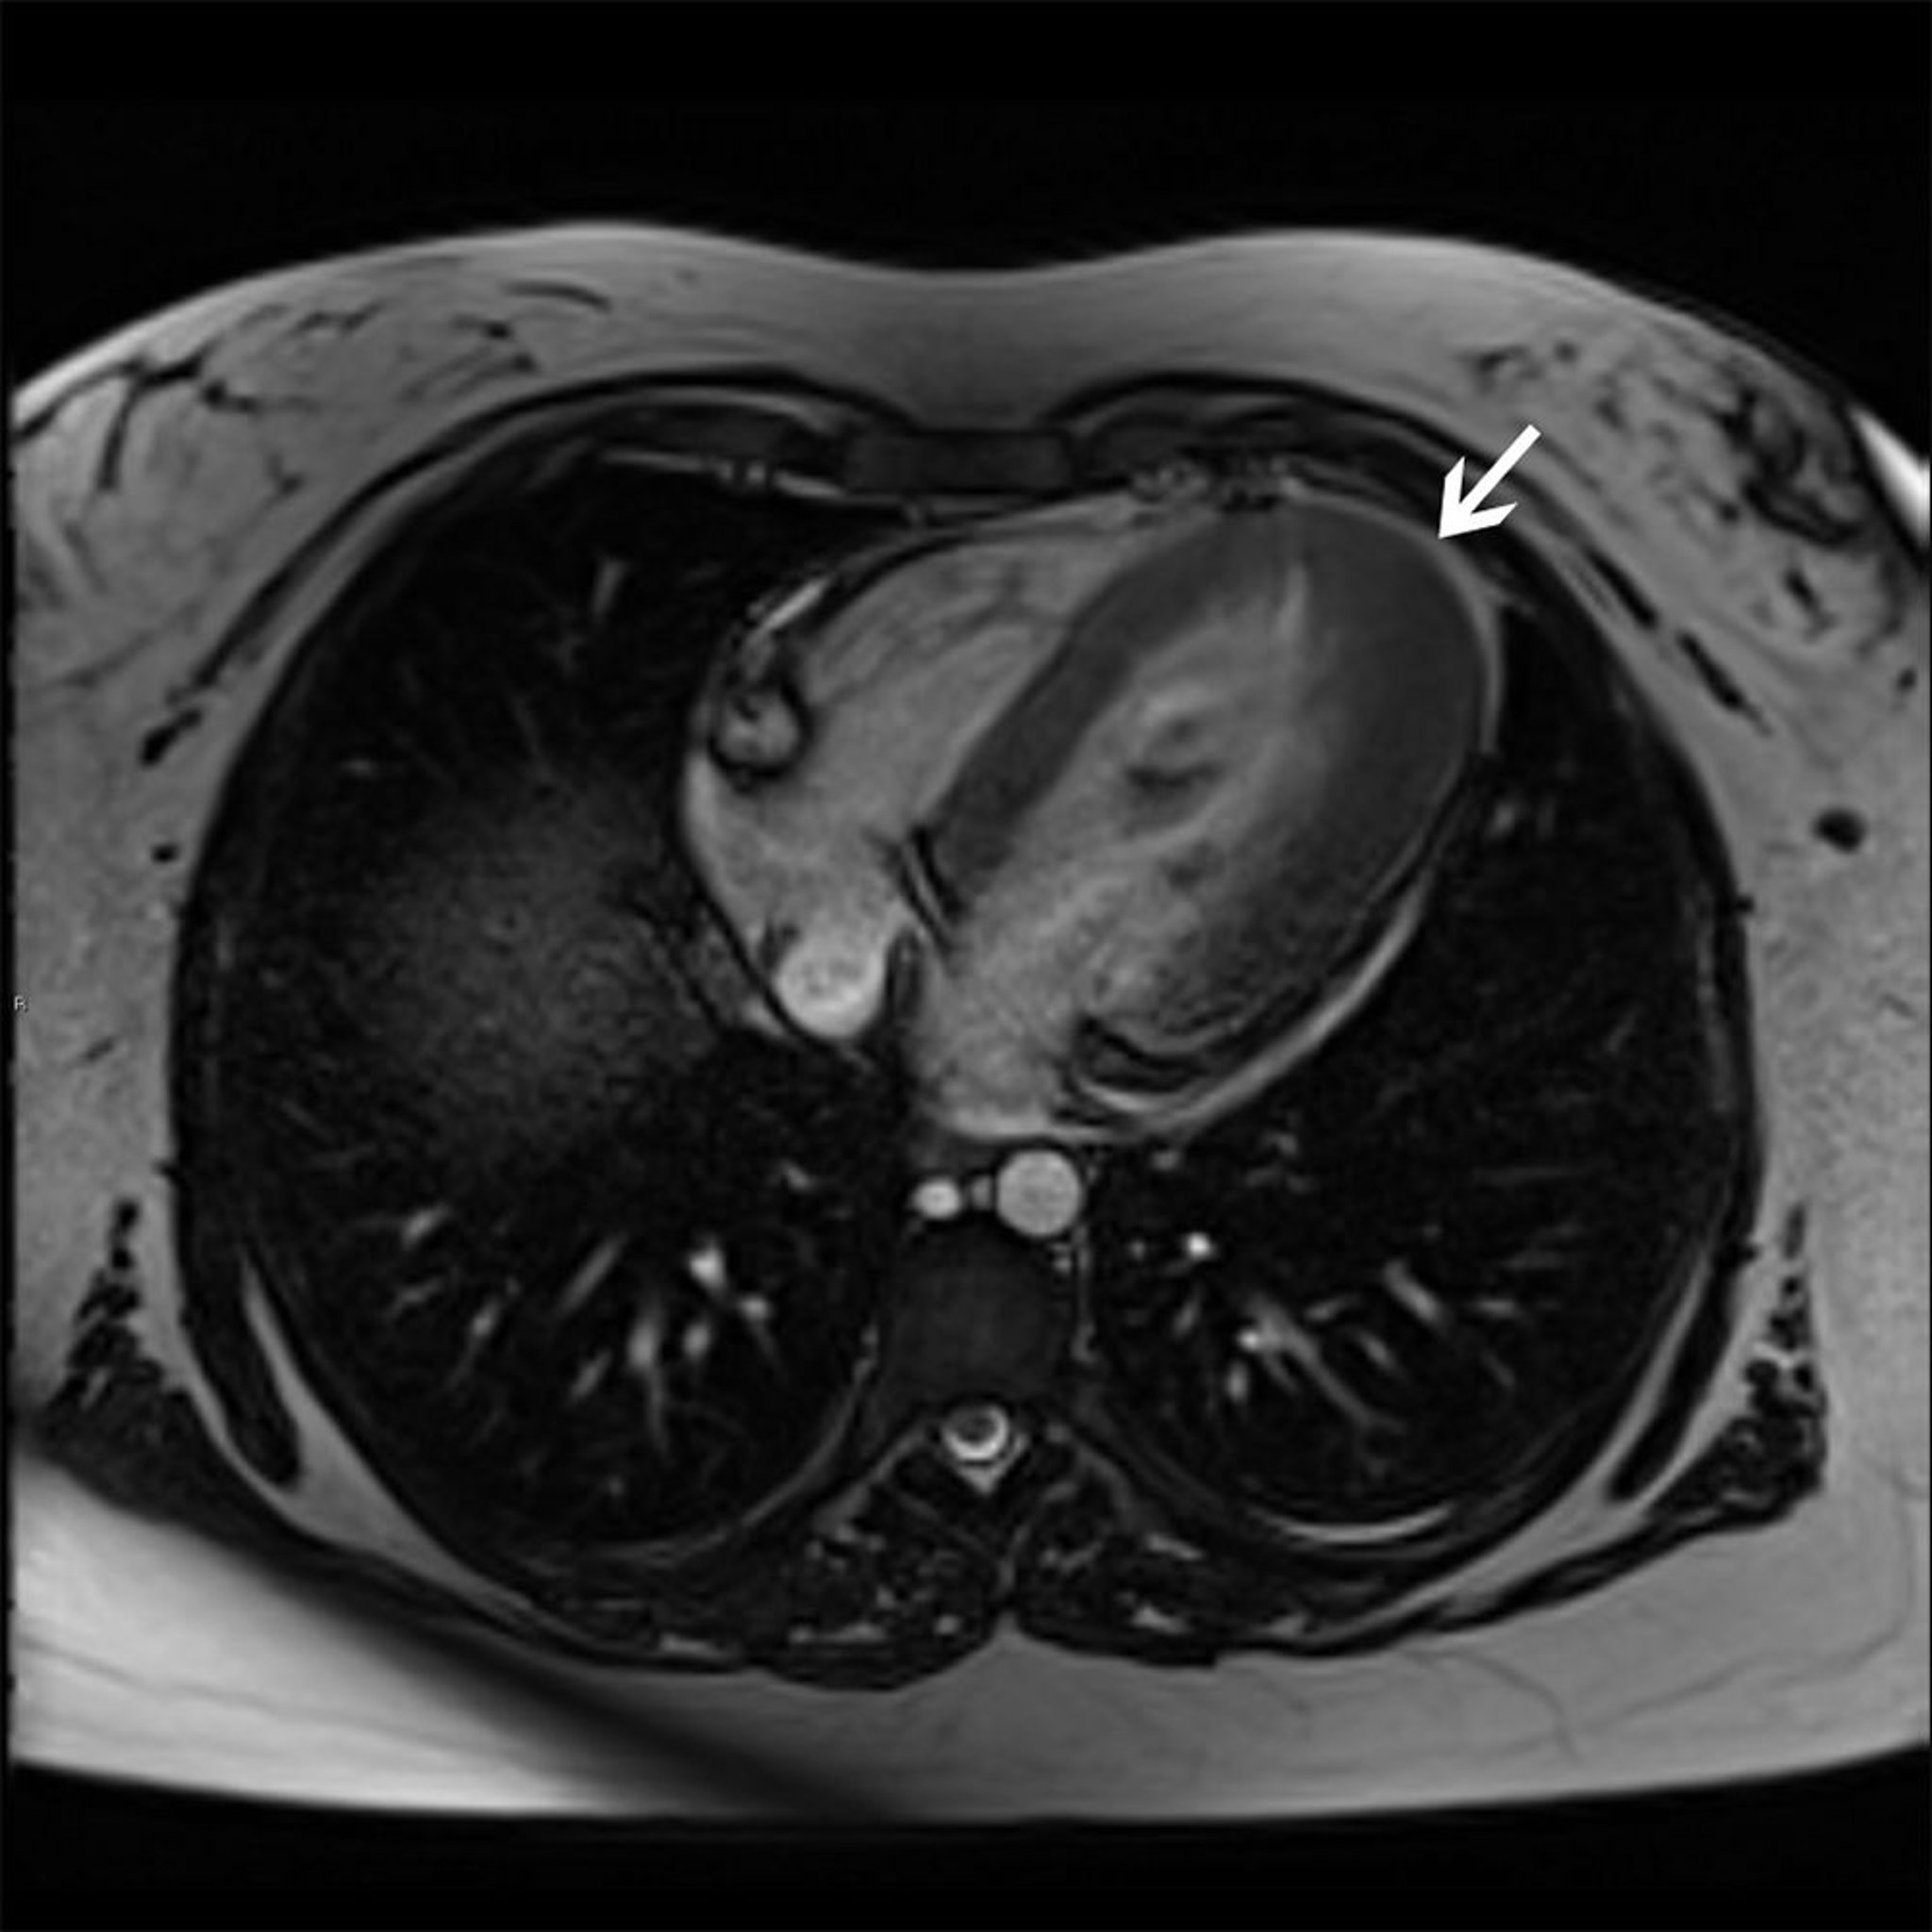

Hypertrophic Cardiomyopathy (Apical Variant)

This cardiac MRI shows apical hypertrophy variant (arrow) of hypertrophic cardiomyopathy.

© 2017 Elliot K. Fishman, MD.